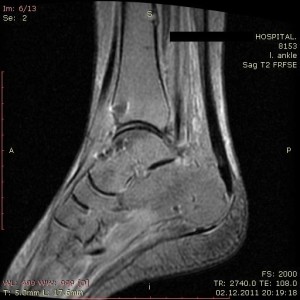

Вовремя выявить некроз кости, возможно, только с помощью двух томографий. Помогут распознать болезнь в самом начале, магнитно-резонансное и компьютерное обследование. Именно подобные методики помогут своевременно выявить болезнь и избежать хирургической операции.

Стадии аваскулярного некроза можно разделить на четыре основные категории: предколлапсная, ранняя коллапсная, поздняя коллапсная и артритная. Стадия предколлапсной: эта стадия характеризуется минимальными симптомами или их отсутствием, а повреждение костей можно обнаружить только с помощью визуализирующих методов исследования, таких как МРТ или рентгенография.